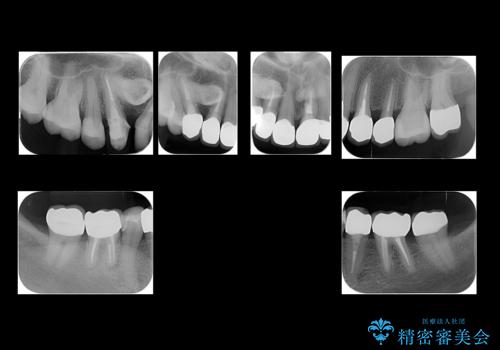

50代女性 銀歯をとって白いつめものに 全体的な治療

- 銀歯や被せ物のやり替えをご希望で来院。悪いところはすべて治していきたいとのことでした。

根の治療を含めてしっかりやり直しを行いました。

本数も多く、時間はかかりましたが、しっかり通いきっていただきました。